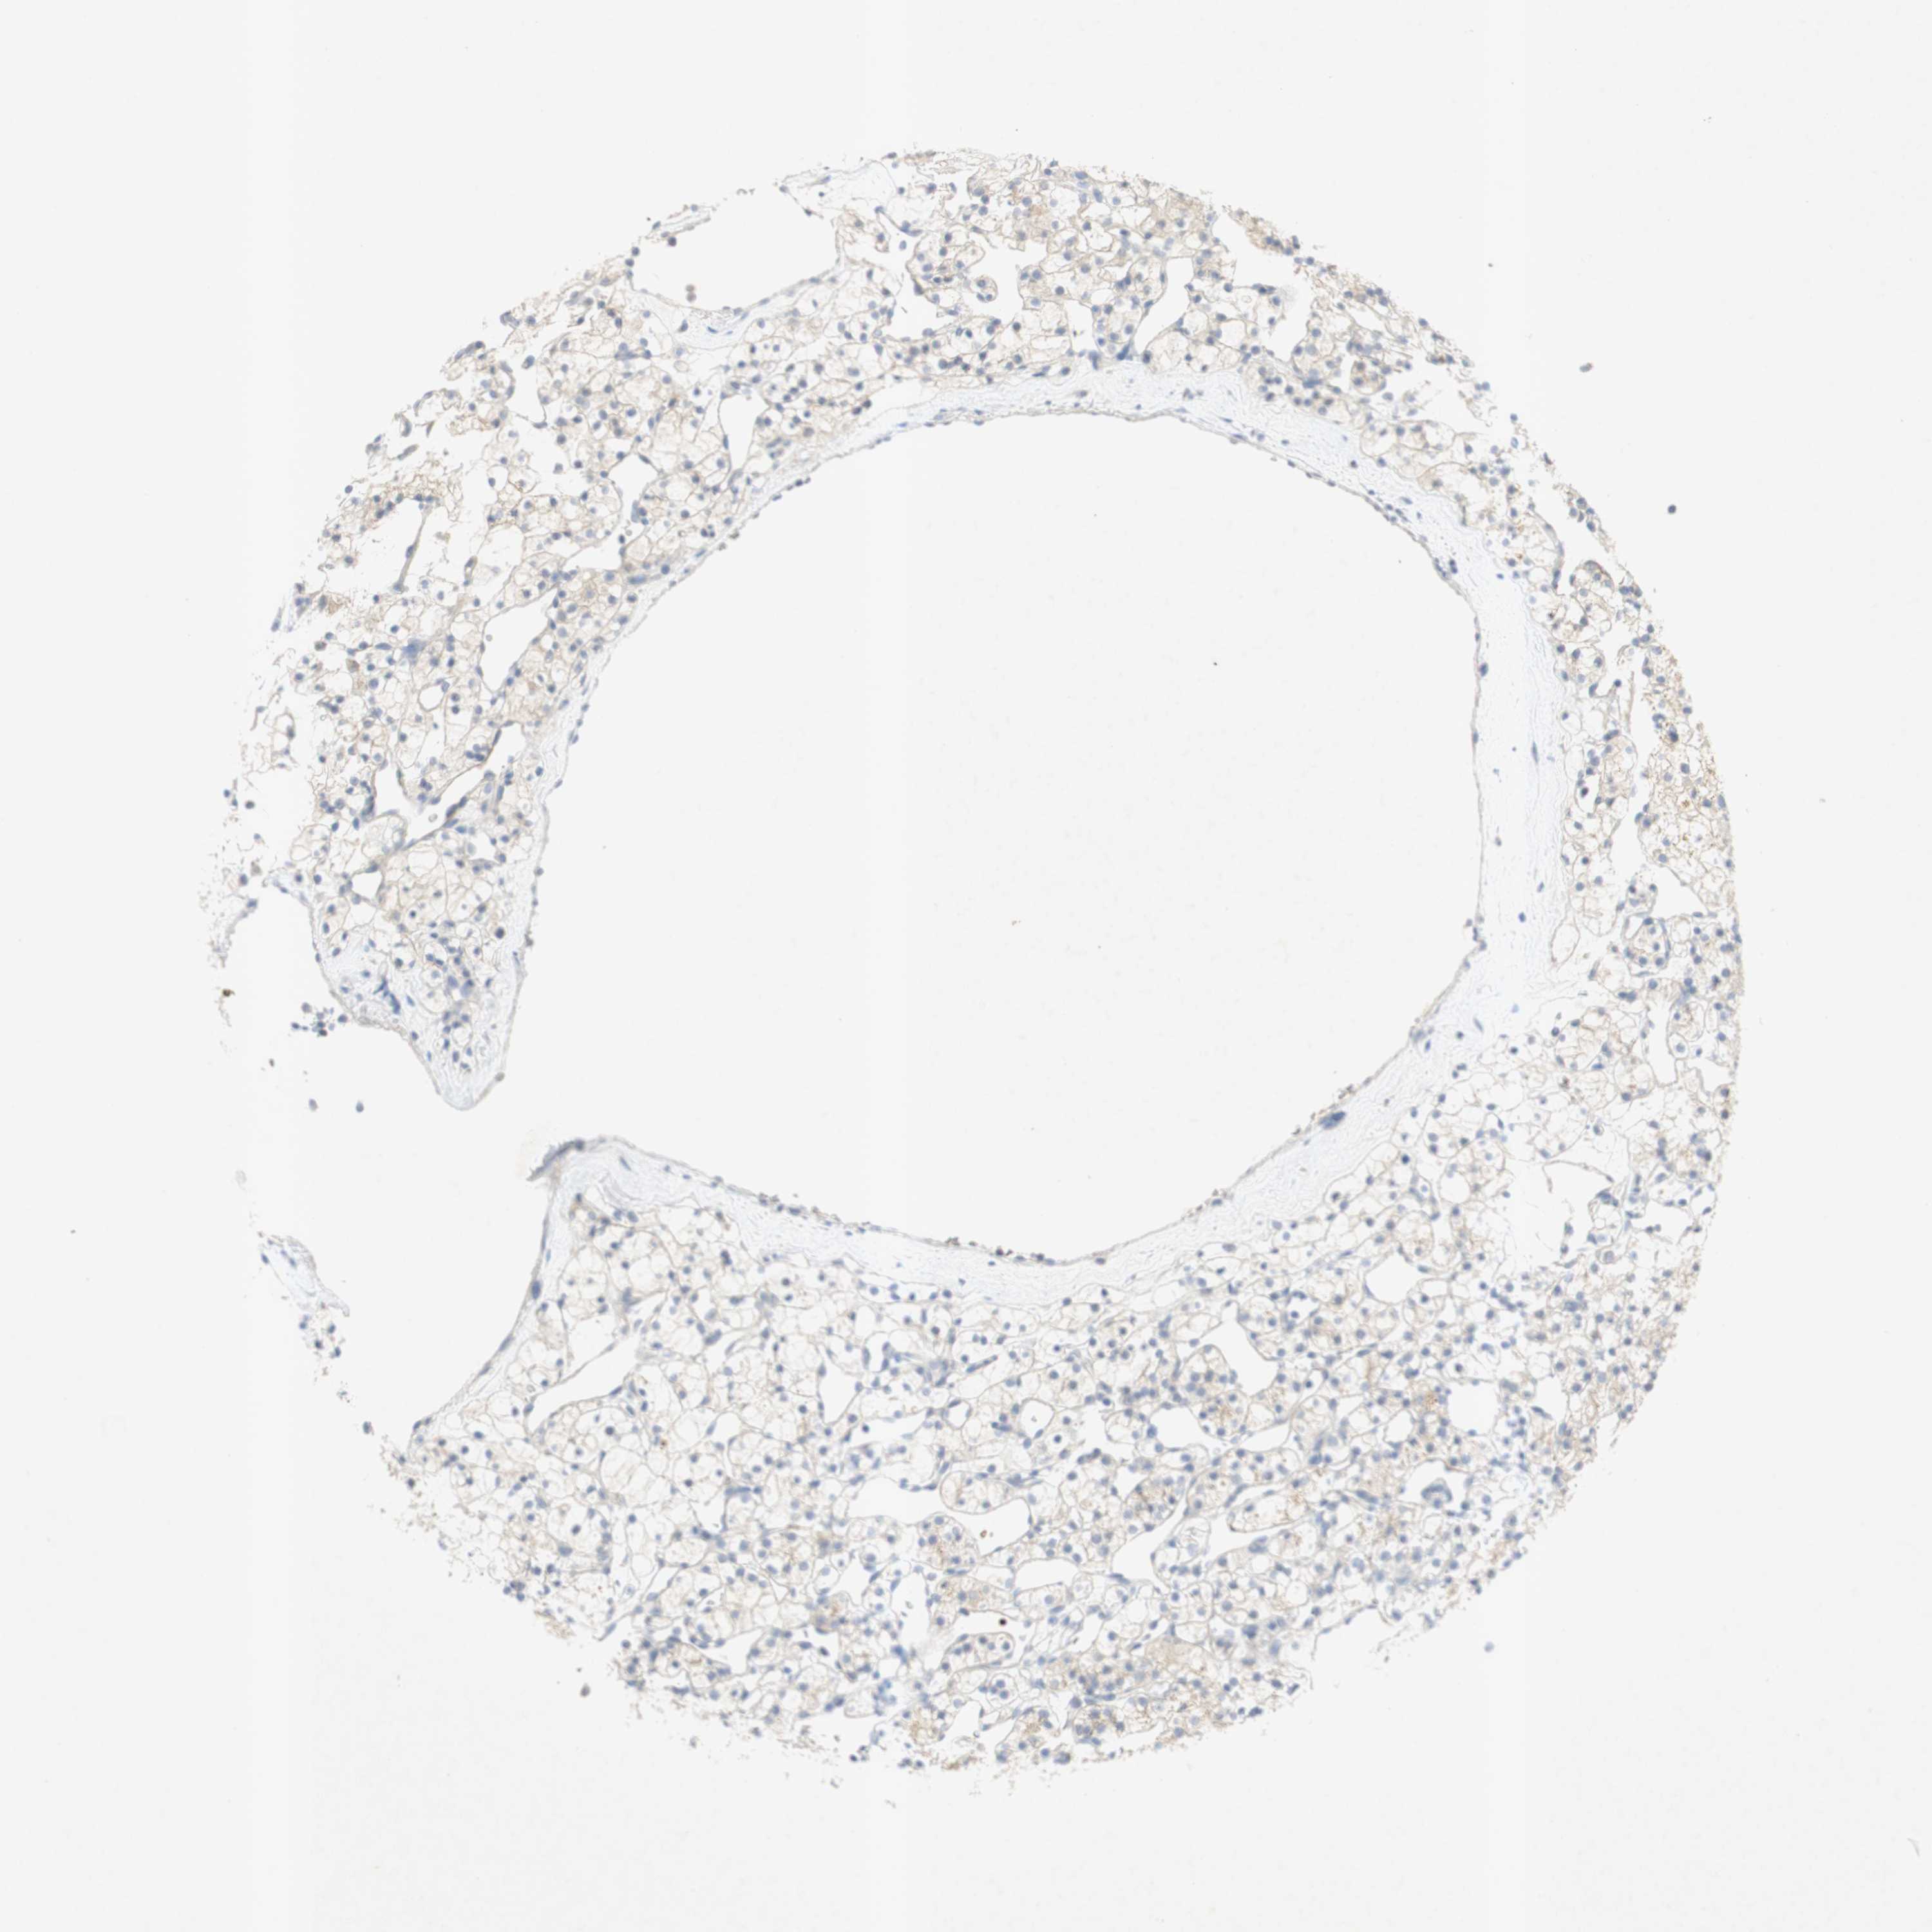

KIDNEY RENAL PAPILLARY CELL CARCINOMA (TCGA) - Interactive survival scatter ploti

The Survival Scatter plot shows the clinical status (i.e. dead or alive) for all individuals in the patient cohort, based on the same data that underlies the corresponding Kaplan-Meier plots. Patients that are alive at last time for follow-up are shown in blue and patients who have died during the study are shown in red.

The x-axis shows the expression levels (FPKM) of the investigated gene in the tumor tissue at the time of diagnosis. The y-axis shows the follow-up time after diagnosis (years). Both axes are complimented with kernel density curves demonstrating the data density over the axes. The top density plot shows the expression levels (FPKM) distribution among dead (red) and alive patients (blue). The right density plot shows the data density of the survived years of dead patients with high and low expression levels respectively, stratified using the cutoff indicated by the vertical dashed line through the Survival Scatter plot. This cutoff is automatically defined based on the FPKM cutoff that minimizes the p-score. The cutoff can be changed by dragging the vertical line or by entering a cutoff value in the square labeled "Current cut-off".

Under the Survival Scatter plot the p-score landscape (black curve; left axis) is shown together with dead median separation (red curve; right axis). Dead median separation is the difference in median mRNA expression between patients who have died with high and low expression, respectively. It is calculated as follows: median FPKM expression of dead patients with high expression - median FPKM expression of dead patients with low expression. This is intended to aid the user in visually exploring custom cutoffs and the associated p-scores and dead median separation.

Individual patient data is displayed and can be filtered by clicking on one or more of the category buttons on the top of the page. Categories describing expression level and patient information include: high, low, alive, dead, female, male and tumor stages. The scale of the x-axis can be toggled between linear and log-scale by clicking on the "x log" button. Mouse-over function shows TCGA ID, patient information and mRNA expression (FPKM) for each patient.

& Survival analysisi

Kaplan-Meier plots summarize results from analysis of correlation between mRNA expression level and patient survival. Patients were divided based on level of expression into one of the two groups "low" (under cut off) or "high" (over cut off). X-axis shows time for survival (years) and y-axis shows the probability of survival, where 1.0 corresponds to 100 percent.

EPO is not prognostic in Kidney Renal Papillary Cell Carcinoma (TCGA)

: N/A

Average pTPM 0.1

Number of samples 282